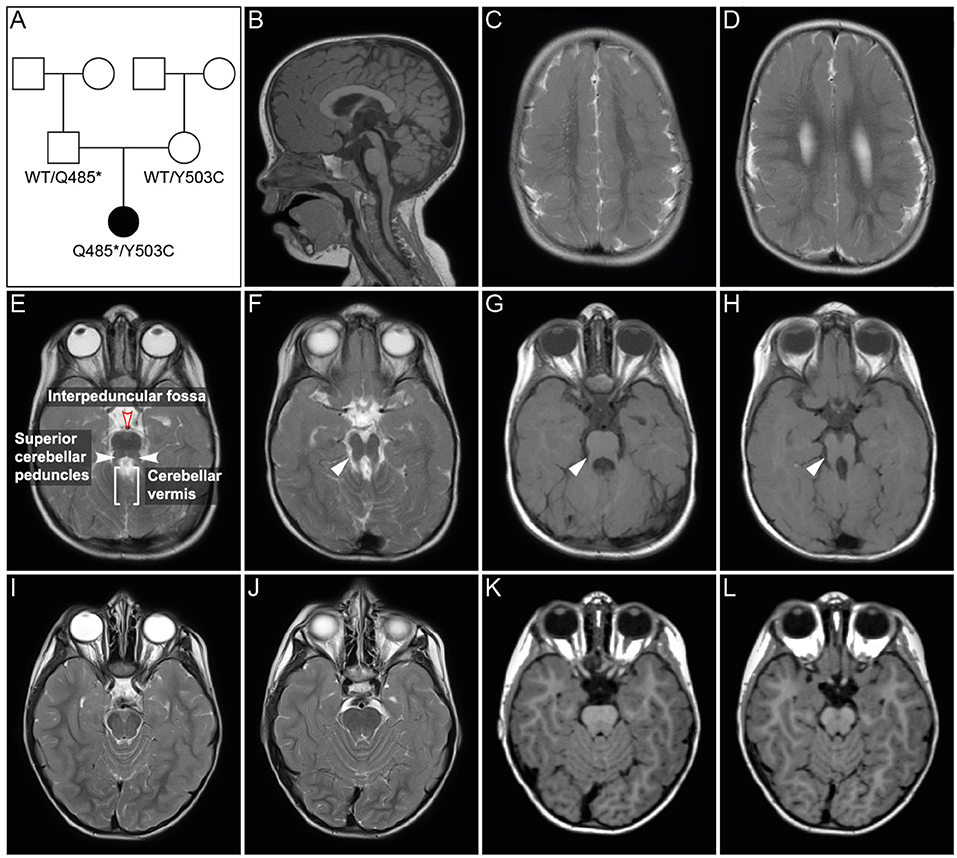

Figure 1. Pedigree and MRI scans. (A) Pedigree of patient family. Black symbol, affected individual; White symbols, unaffected individuals. (B–H) MR imaging of the patient at age 2 years and 6 months. Sagittal (B) and axial (C–H) images showed polymicrogyria in the parietal and temporal region (C,D) and hypoplasia of vermis cerebellum (B,E–H). Axial MR images of cerebellum and brainstem (E–H) showed a mild “molar tooth sign” (marked with white arrows in F–H) due to a deep interpeduncular fossa, prominent and elongated superior cerebellar peduncles and a hypoplastic cerebellar vermis. (I–L) Corresponding MR images of a healthy control